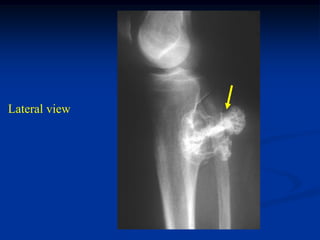

Case #556

55 year male with

enchondroma tibia

Lateral view